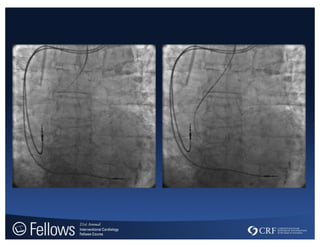

Deep intubation of RCA with JR4

AMPLATZ for Complex PCI

ITS 2011 Transradial Curvesfor Right Coronary – Judkins Right Deep intubation of RCA with JR4